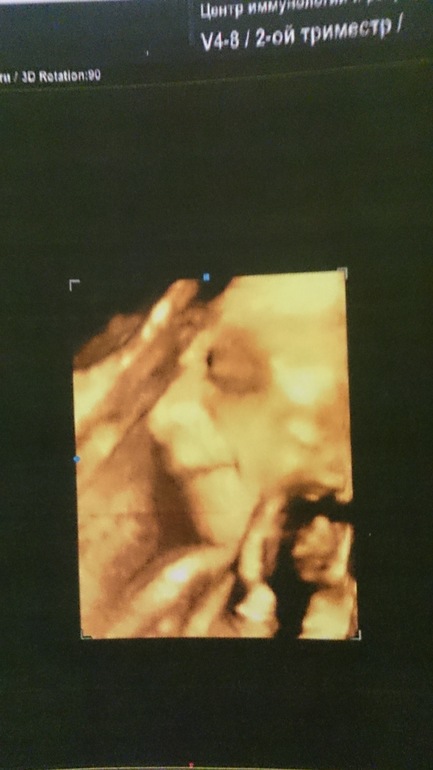

Пузяши наши, ВДМ, тазДевочки успокойте сумашедшую мамашу))))Сегодня было наше 3-е узи,(3д).Нам 30 неделек,по узи тянем на 29,все показатели в норме,все хорошо...но эти страшные фото))))наша крошка была сегодня совсем не расположена к фотосессии,и все время лежала отвернувшись,на узи пробовали ложиться и на бок и на один и на другой,но лицо она нам не хотела свое показывать и поворачивать тоже,в итоге внизу то,что смогли запечатлеть.Накрутила меня невестка,которая мне сказала,что она со своими двумя ходила в 30 недель на 3д узи к этому же врачу и они там уже чуть ли ни как на фото были,что вот практически такими и родились.А я теперь сижу и думаю,неужели мы такие страшненькие будем((((Прям даже расстроилась.Девочки ваши малыши были похожи на узи?

У моего в 30 недель на таких фотках нос приплюснут, как-будто уперся лицом в стенку матки)) мне вообще эти коричневые фотки не очень понравились. И все как-то размазано. А вот в 26 недель, когда ходила на доплер, там распечатали черное-белое изображение, так очень даже! Теперь в рамке стоит. Родился прелестный малыш) по данным снимкам вообще не стоит судить! И вообще для каждой мамы свой ребенок самый красивый)))

ну вы даете!)) страшным кажется, потому что через тонюсенькую кожицу косточки просвечивают. там сала-то трудно пробиваемого нет, вот самые плотные и заметные части( скелет) и видны так хорошо. я подозреваю, что мимимишные фотки, как у вашей невестки, получаются из-за обработки вот таких же снимков спецпрограммой. потому что иначе у меня никак не складывается - либо спецпрограмма, либо туфтовый узи-аппарат. это все-таки медоборудование, а не фотосалон.)))